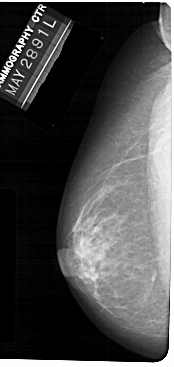

A_1304_1.LEFT_CC

LEFT_CC LINES 5491 PIXELS_PER_LINE 2596 BITS_PER_PIXEL 12 RESOLUTION 43.5 NON_OVERLAY